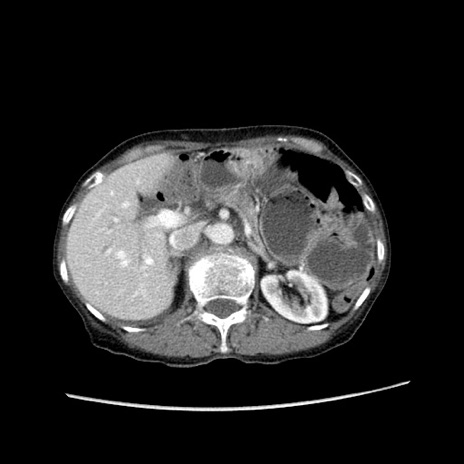

症例25(横断像)

【症例】80歳代女性

【主訴】胸のつかえ感

【現病歴】約9時間前に食後から胸のつかえた感じあり、嘔吐あり、来院。

【既往歴】胃癌(全摘)、胆摘、虫垂炎

【身体所見】心窩部に圧痛あり、反跳痛なし。

【データ】WBC 5700、CRP 0.05